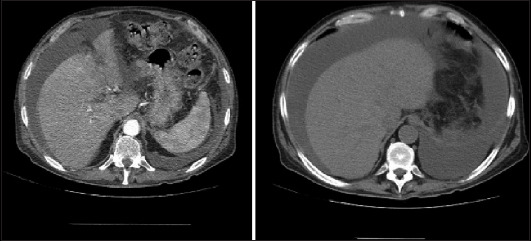

Abstract Image